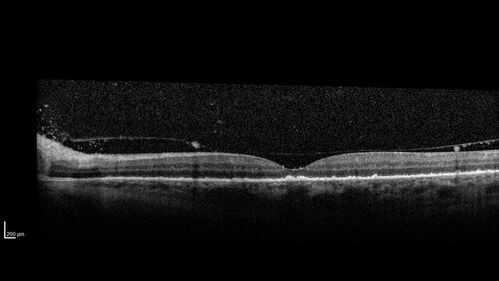

Severe Syphilitic Placoid Chorioretinitis

68 year old man 3 months ago the vision started fading in both eyes.  Just sitting here he can see some light out of his right eye. The patient denies any recent illness or travel.

VA: OD: LP, OS: 4/200

IOP: 9, 13

Anterior segment: 1+ cell/ 2+ flare OU and 2+ NS and anterior vitreous cells

Labs Reactive RPR 1:256, FTA-ABS - reactive - Patient was admitted to hospital for IV PCN and recovered vision almost completely in the left eye and some in the right eye.

See line scans for recovery